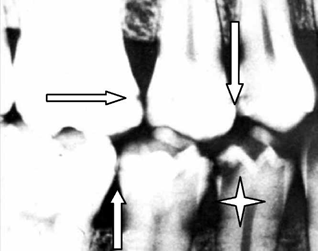

La acción ácida del metabolismo de las bacterias que colonizan la superficie, ataca especialmente los defectos de la estructura del esmalte, penetrando rápidamente a la unión amelodentinaria, propagándose en forma de triángulo invertido (Figura 1).

Cuando la desmineralización predomina, la lesión cariosa produce una cavidad, pero la remineralización continuamente estimulada puede detenerla, teniendo entonces lesiones activas versus inactivas. La remineralización convierte a estas últimas, en alteraciones que no requieren de tratamiento invasivo, ya que sólo necesitan de medidas que estimulen el proceso de remineralización, por lo que la meta terapéutica debería centrarse en prevenir las lesiones iniciales del esmalte que no requieren de excavación de la estructura dentaria, evitar la preparación de cavidades y la colocación de restauraciones (Figura 2).

Figura 2 Las flechas muestran caries de esmalte, que pueden cicatrizar y la estrella una lesión de caries que puede detenerse y tratarse con mínima intervención.